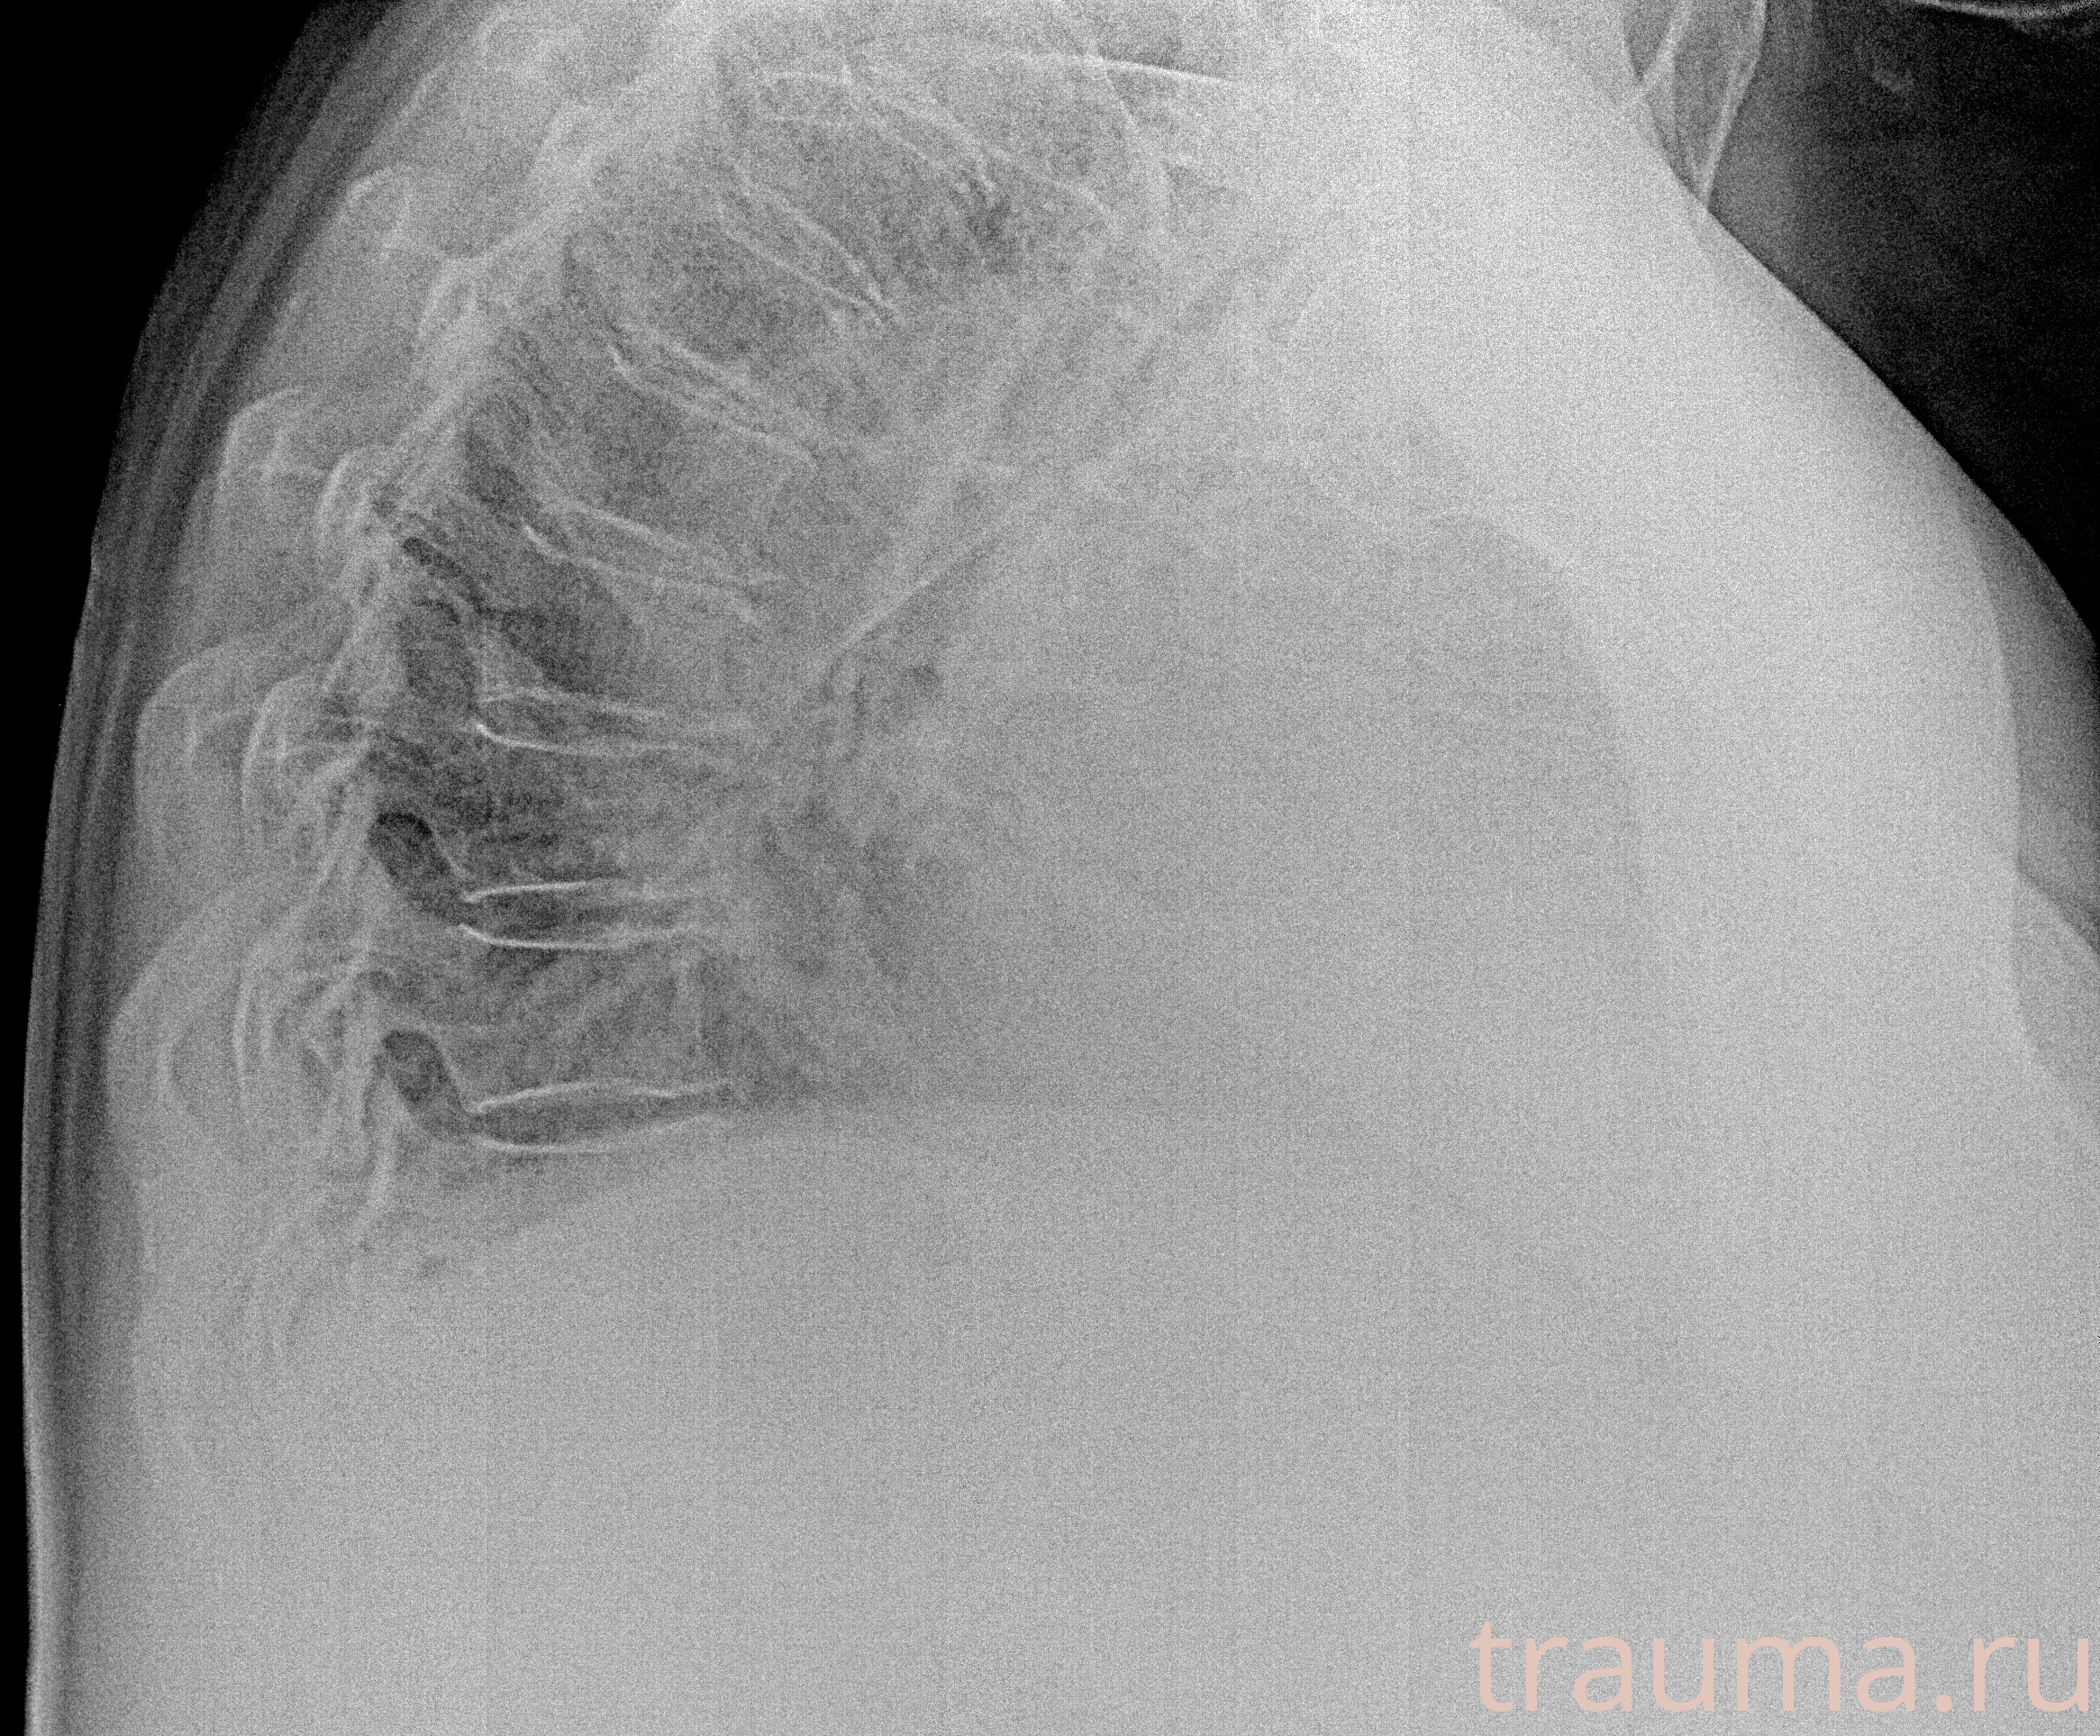

Рентген на дому: по вашему адресу приезжает врач-рентгенолог, травматолог-ортопед с мобильным рентгеновским аппаратом, проводит диагностику травмы или заболевания, делает необходимые рентгенограммы, дает рекомендации по дальнейшему лечению. Получить качественные снимки в домашних условиях возможно благодаря уникальной методике, разработанной МосРентген Центром для института  Склифосовского